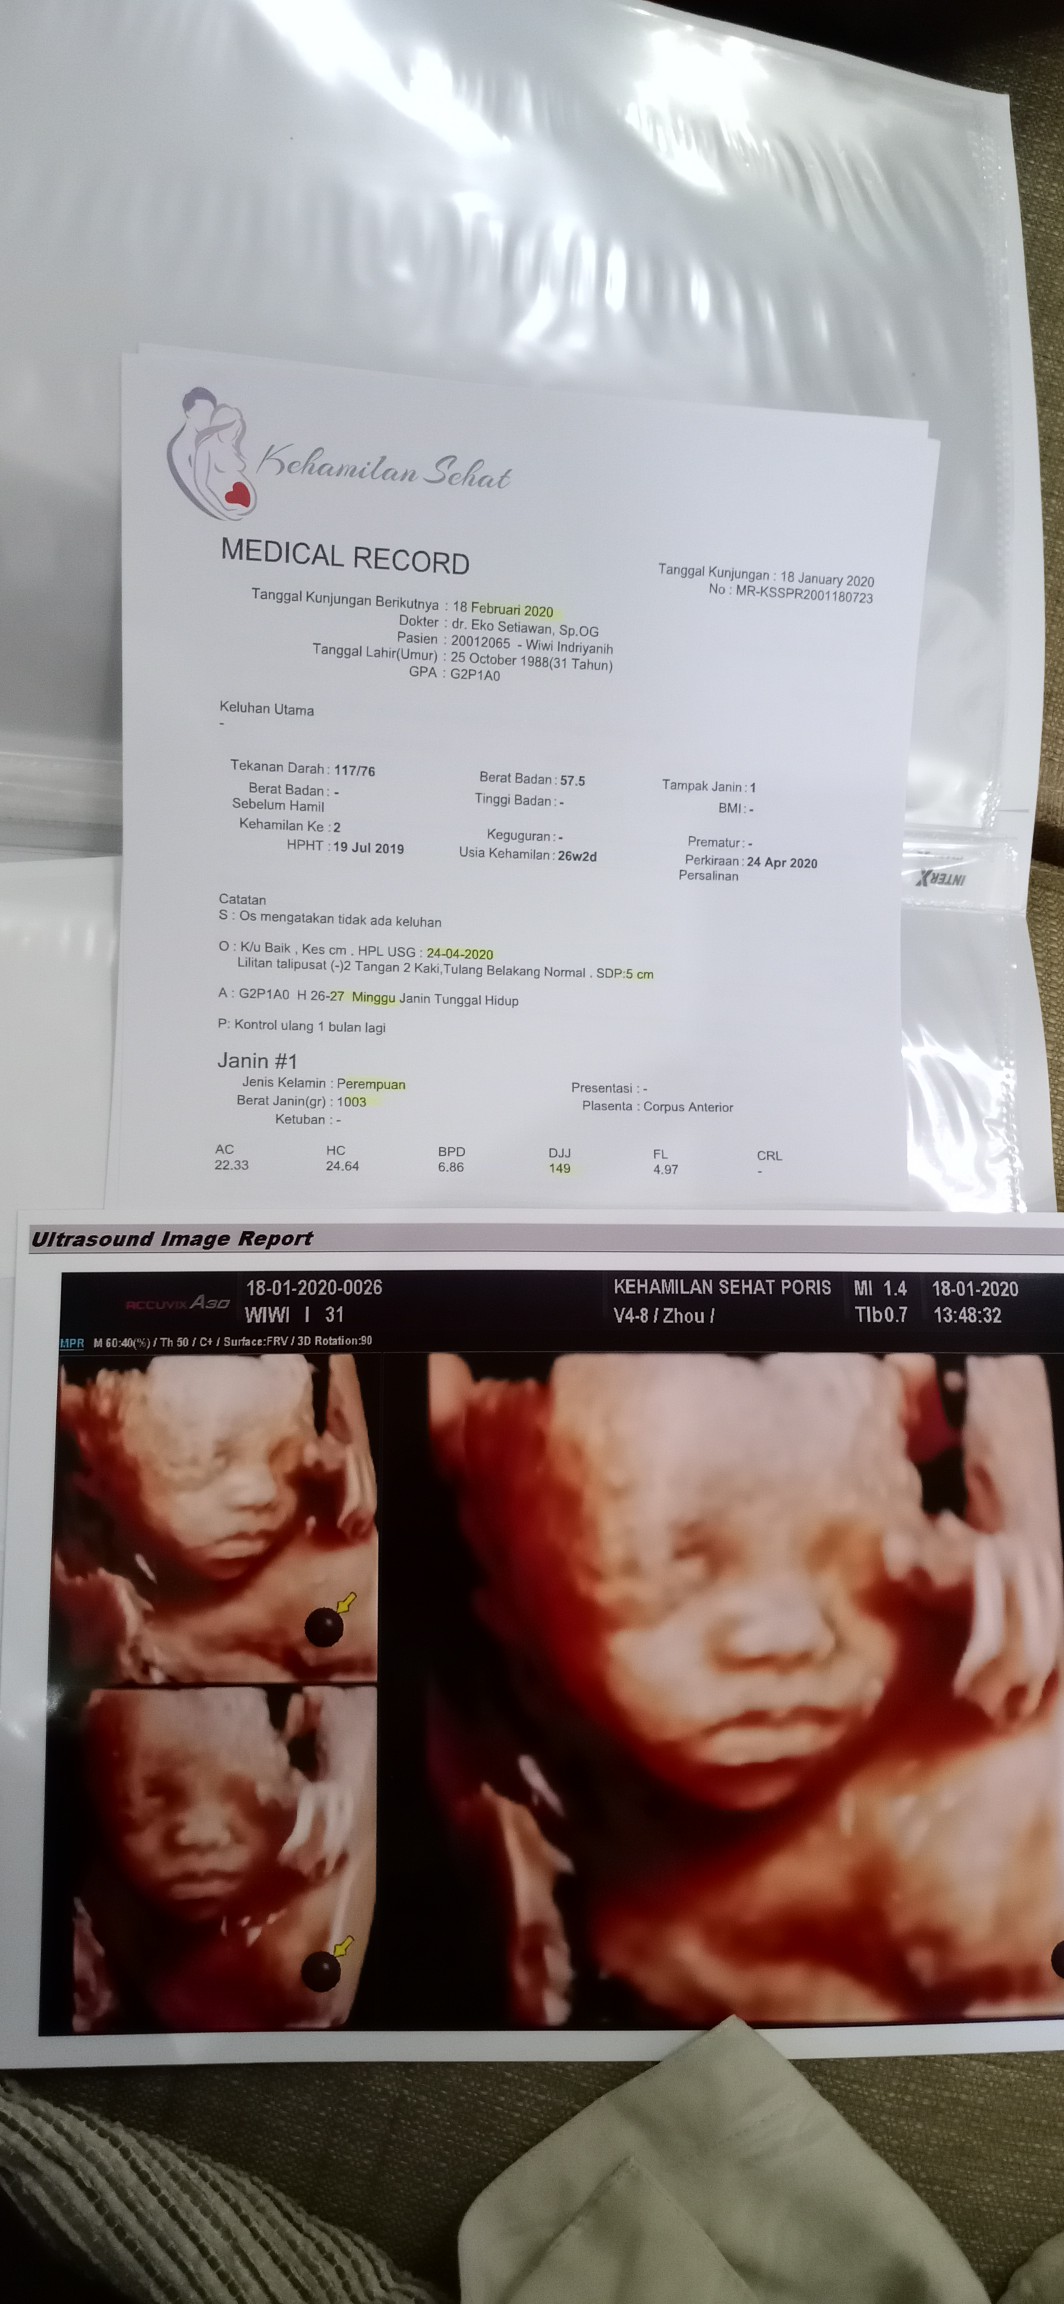

USG

Halo bunda. Saya baru usg malem ini dan saya USG pake 2D. Nah pertanyaan saya berapa sih biaya USG 4D?